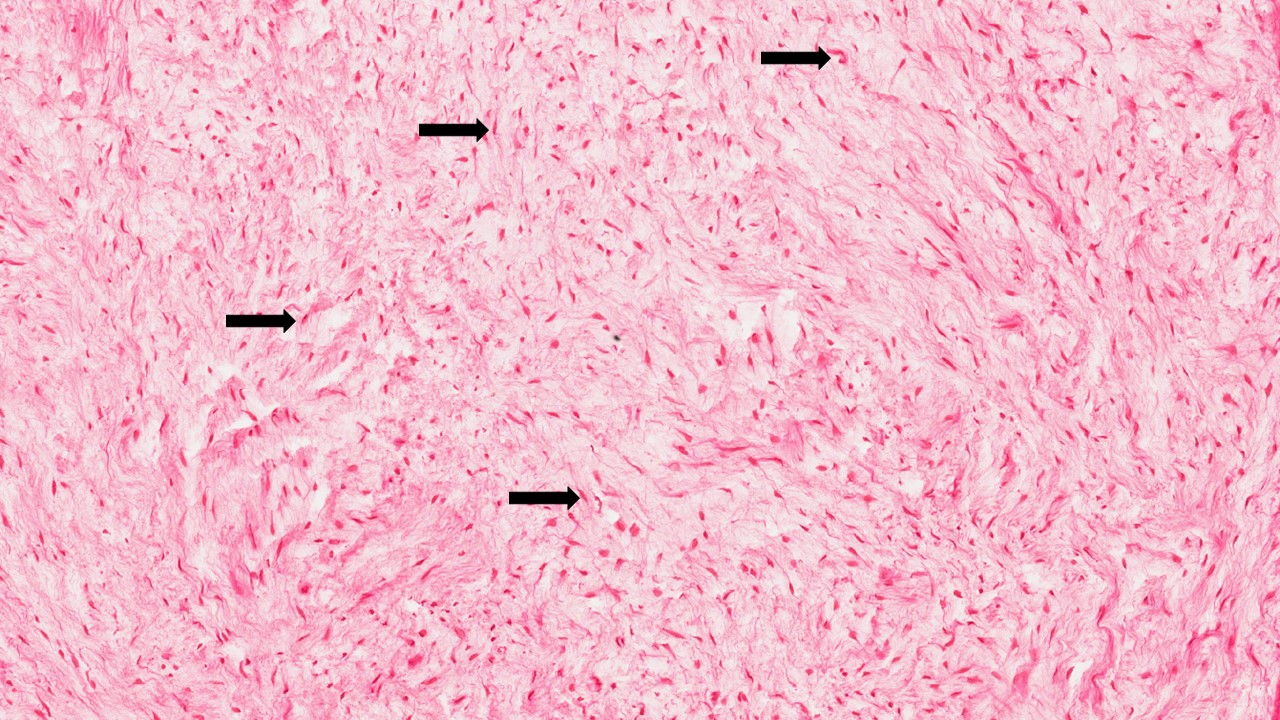

São tumores benignos originados do ectomesênquima odontogênico, exibem uma grande semelhança microscópica com a porção mesenquimal de um dente em desenvolvimento.

Descrição microscópica:

Microscopicamente, o tumor é composto por células mesenquimais de formato estrelado, fusiforme ou arredondado dispostas em um estroma abundante, frouxo e mixóide que contém somente algumas fibrilas colágenas.

Dados importantes para diagnóstico:

- Tecido conjuntivo frouxamente arranjado e organizado com pouco colágeno;

- Fibroblastos fusiformes estrelados neoplásicos (setas).